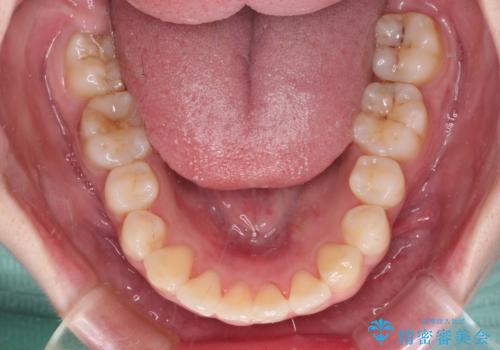

前歯のデコボコをインビザラインできれいに整える

前歯の捻れを改善するとともに、口元が少しでも引っ込むように治療計画を立て、仕上げることができました。

長時間の装着や、定期的な来院がままならず、想定よりも長期間の治療となってしまいました。